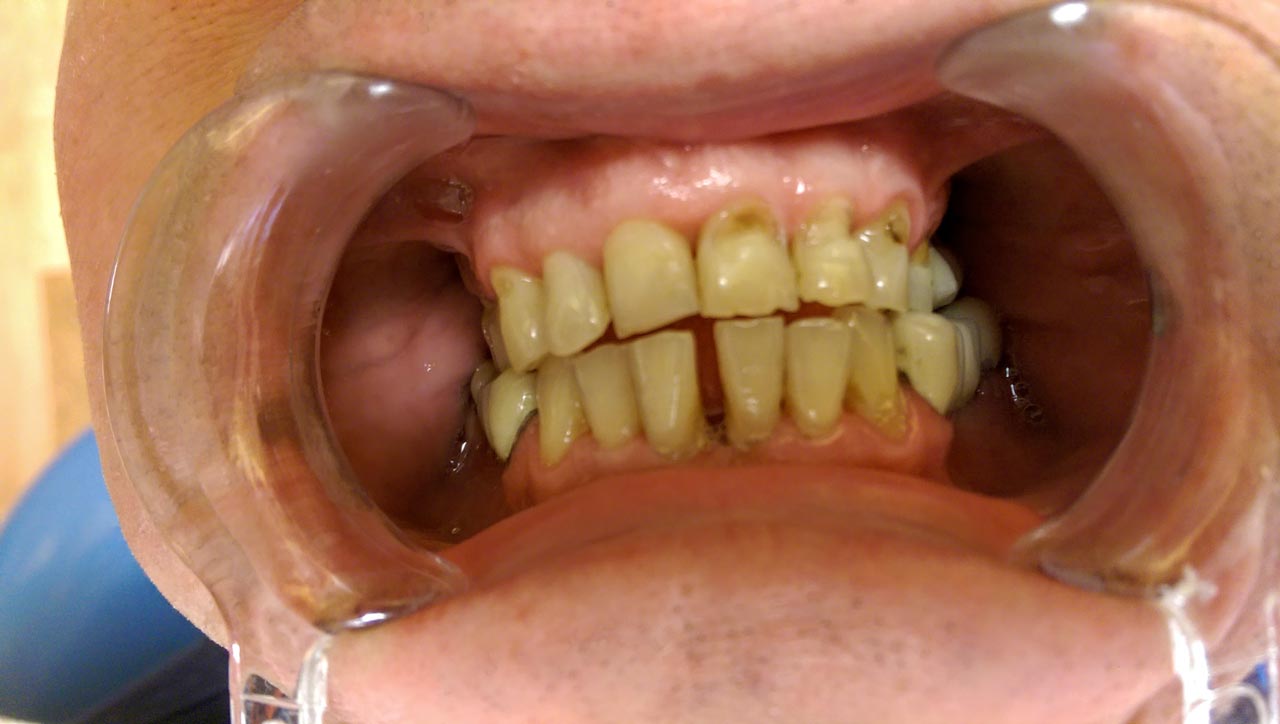

Teljes szájüregi rehabilitáció két lépésben

Ismét egy teljes szájüregi rehabilitáció két lépésben. Először az alsó fogak lettek kihúzva és azonnal implantálva, híddal ellátva, majd később a felső. IHDE svájci azonnal terhelhető implantátumok és cirkónium hidak. Dr. Kelemen Péter és a Symbion Fogtechnika közös munkája.